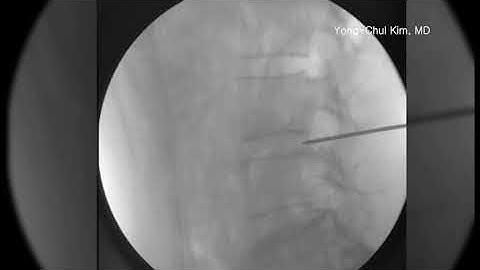

Lumbar C-arm Lab Simulation